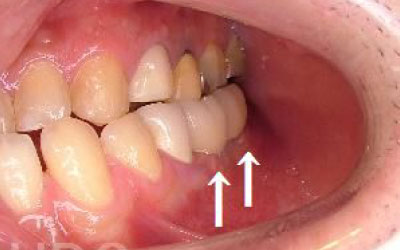

2 歯が傾いてくる、落ちてくる

歯はお互いに支え合ってバランスを保っています。つまり、歯が抜けるとその支えがなくなり、抜けた部分の隣の歯が傾いたり、上の歯が下にずれてくることがあります。